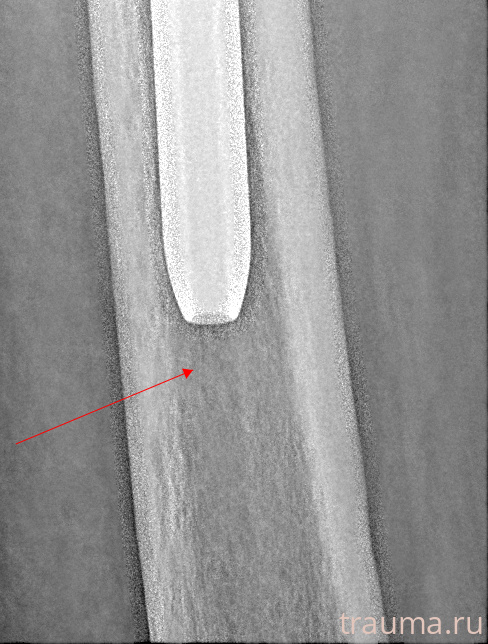

Рентген на дому: по вашему адресу приезжает врач-рентгенолог, травматолог-ортопед с мобильным рентгеновским аппаратом, проводит диагностику травмы или заболевания, делает необходимые рентгенограммы, дает рекомендации по дальнейшему лечению. Получить качественные снимки в домашних условиях возможно благодаря уникальной методике, разработанной МосРентген Центром для института  Склифосовского